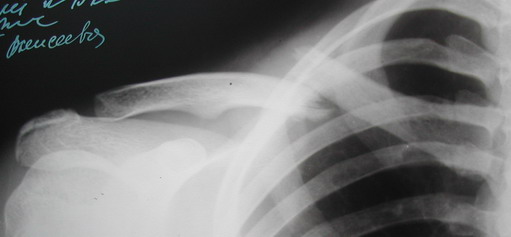

Во время стажировки в Австрии не мог не поинтересоавться, как австрийские хирурги лечат переломы ключицы. Оказалось, при переломах без смещения или с небольшим смещением накладывают восьмиобразную повязку, в остальных случаях выполняют остеосинтез пластинами.

Хотя с точки зрения кожных рубцов на видном месте, рамка Чижина и аппарат имеют явное преимущество. Но в ущерб "качеству сна"...